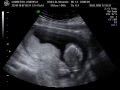

Ecografia 15 semanas 2 dias de embarazo!!! Es un. Aqui les dejo la 3 ecografia de mi bebe. Mide 18 cm de largo, el diametro de su cabecita es de 3,17 cm y pesa 125 gramos. Y definitivamente es un varon